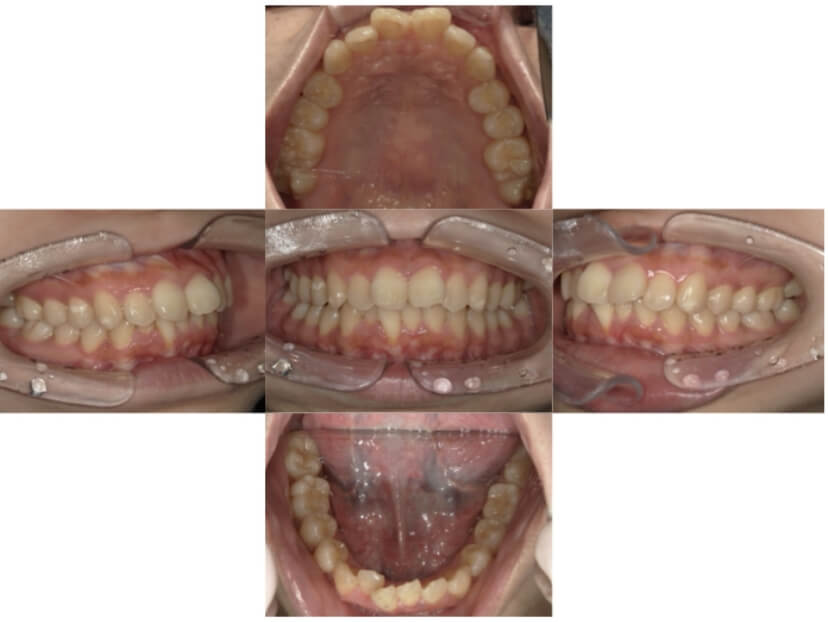

症例1

上顎前突、叢生

抜歯

ブラケット矯正

上下顎叢生、上顎前突(出っ歯、上下の前歯のガタガタ)のケースです。

装置はラビアル(上下表側)で、上顎の小臼歯を2本抜歯を行っています。抜歯したスペースを使って、上の前歯の後方移動と叢生(ガタガタ)と出っ歯の改善を行っています。下は歯と歯の間にIPR(隣接面削合)を行い、スペースを確保し、叢生の改善を行っています。

主訴 前歯のガタガタと出っ歯が気になる。

年齢・性別 47歳 女性

お住まいの地域 神奈川県川崎市

治療方針 抜歯スペースおよびIPRを利用して上前歯の叢生(ガタガタ)の改善

抜歯部位 上顎左右第一小臼歯

使用装置 ラビアル(上下表側)、顎間ゴム

治療期間 2年0か月

治療回数 15回

リテーナー クリアリテーナー

AFTER